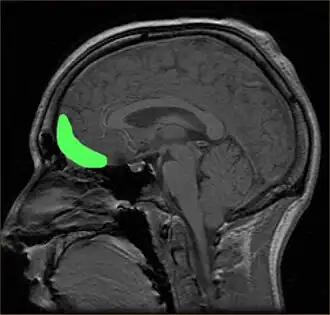

![]() Approximate location of the OFC shown on a sagittal MRI | |